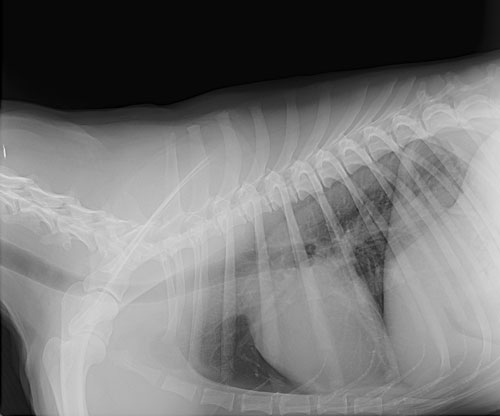

Radiographs (X-Rays)

Our veterinary hospital has the in house capabilities of performing radiographs on your pet. Radiographs can be used to diagnose fractured bones, intestinal foreign bodies, bladder stones, and can be a useful tool in cardiac disease